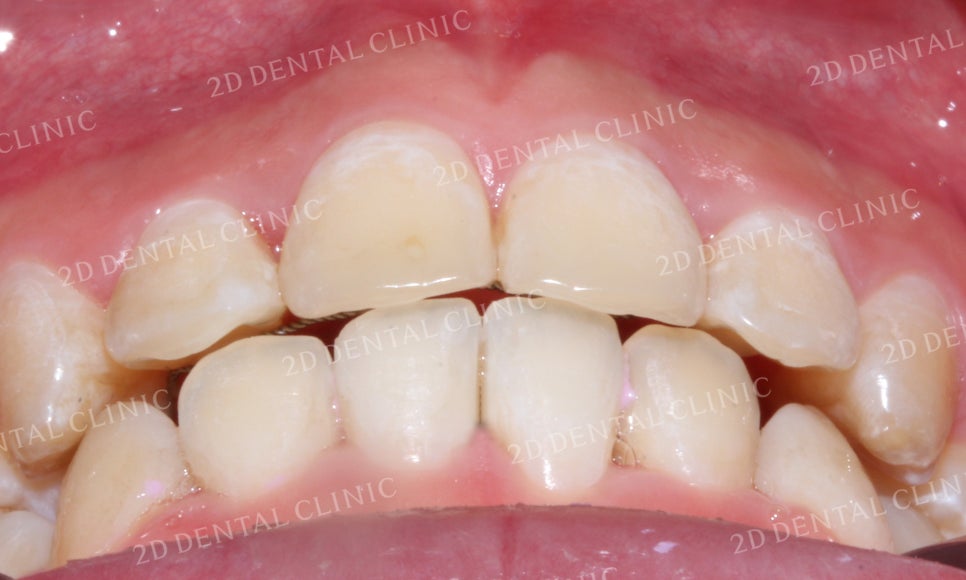

전치부 치아의 모습을 보시면

돌출된 중절치 뒤로 맹출 되어 있던

측절치가 교정 후 고르게 바뀐 모습입니다.

삐뚤거림이 심하던 하악의 전치부 또한

가지런하게 배열된 모습입니다.

돌출앞니 전체교정 후